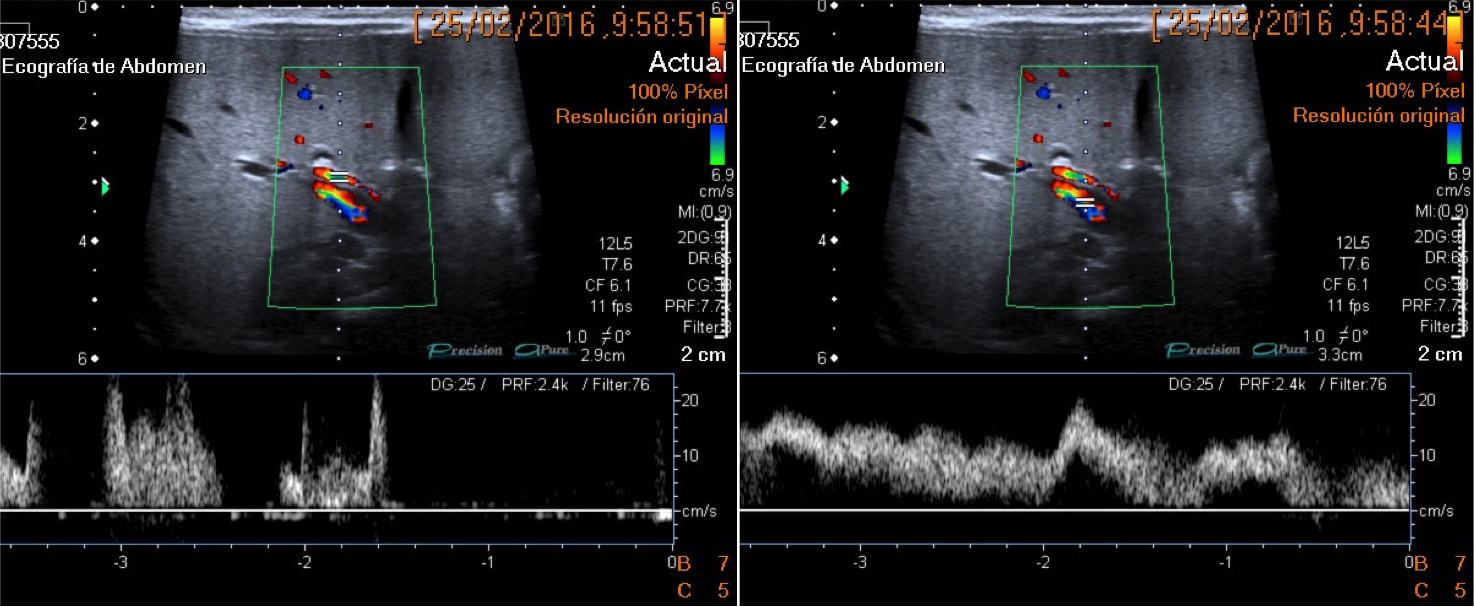

Ecografía:

- Signo de la cuerda triangular ecogénica: es una estructura ecogénica tirangular o tubular compuesta por tejido fibroso localizada craneal a la bifurcación de la vena porta. Consituye el mejor signo ecográfico para el diagnósitco. Tiene una S y E del 93 y 83 % (Choi et al).

- Arteria hepática de calibre aumentado.